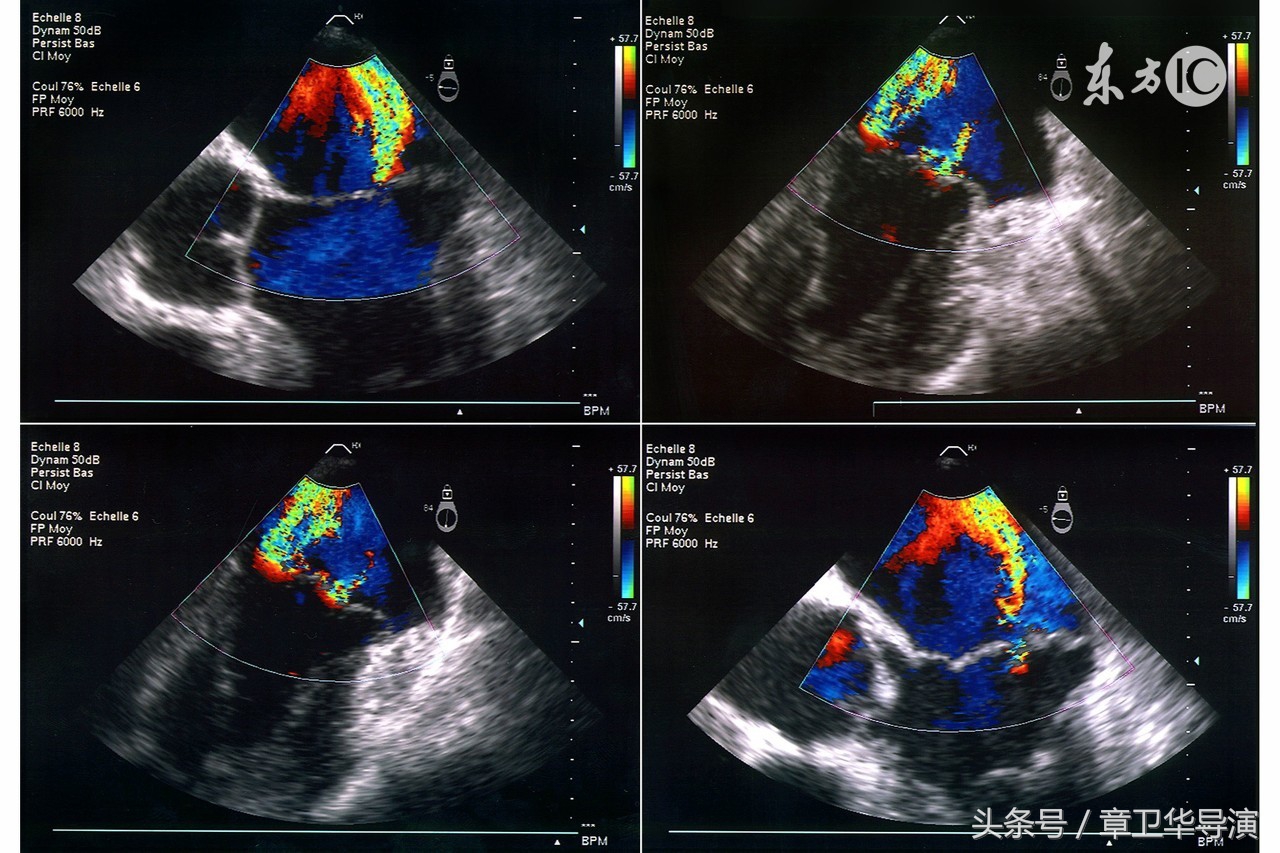

7、什么是多普勒超声?

这个检查是在怀孕阶段通过经腹超声完成的。声波用于计算胎儿脐带或者其他血管中的血流,也用于监测胎心。

8、什么是三维和四维超声?

三维超声检查其实就是由在许多不同的角度拍摄的很多二维图像整合而成的。四维图像则类似于三维图像,只不过它可以展示胎儿的动态表现。在孕期,只有在排除胎儿畸形时才使用三维超声,所以近年来,又出现了三维超声和超声造影检查等新技术,均在迅速发展中,目前临床上三维超声主要用于产科对胎儿的检查。